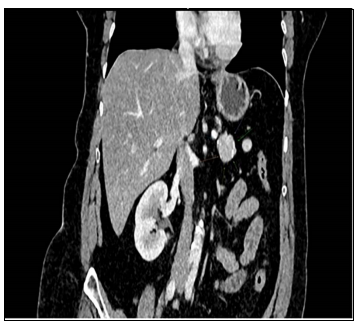

腹部增强多排CT扫描显示胰尾部有一大小为30*21*25 mm的富血供肿块(图1),最初怀疑为神经内分泌肿瘤。

图1. 腹部增强CT扫描显示胰尾部边界清晰的孤立性富血供肿瘤

病灶在动脉期呈早期强化,静脉期持续摄取造影剂,无胰管扩张或邻近结构侵犯,也无区域淋巴结肿大或远处转移的影像学征象。